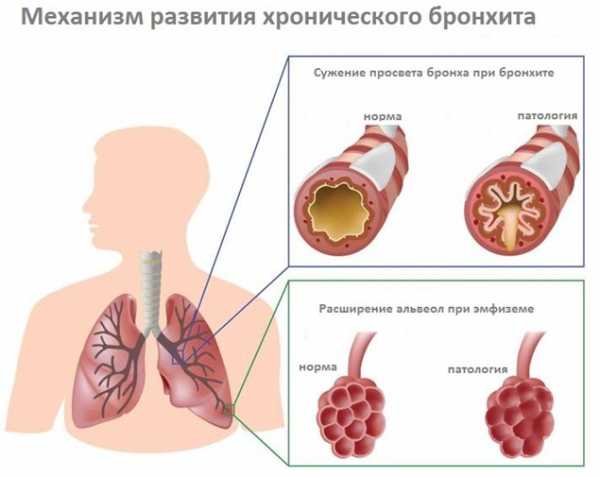

Бронхит может быть острым, возникшим впервые или повторяющимся не чаще раза в три года. Если же воспаление бронхов возникает чаще, говорят о хронической форме заболевания. Также бронхит бывает обструктивным и необструктивным.

При обструктивной форме возникает спазм бронхов и они перестают проводить воздух в лёгкие (фото). При необструктивной форме такого не происходит.

Воспалительное заболевание слизистой оболочки бронхов называется бронхитом. Вследствие нарушения воздушной циркуляции происходит отек бронхов, появляется одышка, кашель с выделением мокроты. Бронхит может быть следствием ОРВИ, простуды, а также других заболеваний.

При плохом лечении острого бронхита она может перейти в хроническую форму бронхита. Кашель со скудной мокротой, одышка при физической нагрузке, периодическое повышение температуры – симптомы хронического бронхита, который имеет тенденцию к обострению в сырое и холодное время года.

Лекарства при бронхите назначаются в зависимости от формы и стадии заболевания. При острой форме лечение нацелено на уничтожение возбудителя, а при хронической – на выведение мокроты. Хронический бронхит нередко называют «бронхитом курильщика», так как он возникает при продолжительном курении. Со временем бронхит курильщика может усугубляться, приводить к спаданию альвеол и развитию эмфиземы легких.